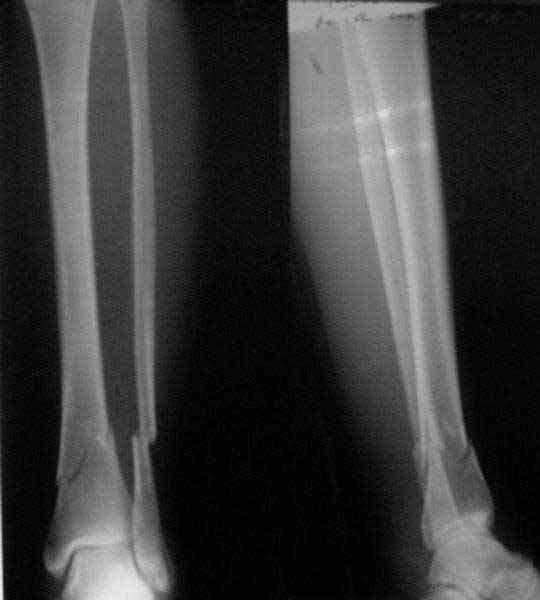

There are some more tricks which allow not to plate the fibula and provide good alignment and stability. A small wire distractor can provide alignment and restore length of both tibia and

fibula. Angular stability of the tibia is provided by insertion of more than two conventional medial-lateral locking screws. To maintain the position of the fibula perQ insertion of a single position screw often could be enough. I bet the articles didn't analyze the options.

A typical case is attached, also an image with intra-op reduction obtained by a small wire distractor, in the moment of insertion a Poller wire in AP direction. Fixation by a SIGN nail. Despite the fibula was not fixed healing was obtained with the unchanged alignment.